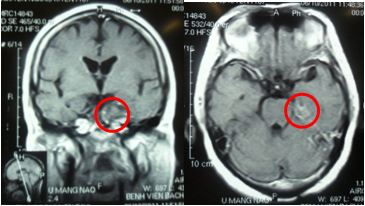

Hình 1: Hình ảnh u màng não trên phim chụp MRI, trước điều trị: U có kích thước 3x 5 cm, chèn ép động mạch cảnh trong. Bệnh nhân bị đau nửa mặt trái, giảm thị lực mắt trái.